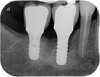

Cette technique permet ici de remplacer la dent par un implant le jour même de son extraction.

En effet, cette dent qui présentait une carie sur sa racine et qui ne pouvait pas être soignée, a été extraite. Le jour même, un implant a été posé dans le « trou » laissé par la dent. Aucun point de suture n’a été nécessaire. Les suites opératoires sont nettement améliorées : pas de douleur, pas de gonflement !

Cela a également permis de gagner trois mois de cicatrisation. L’os se résorbe beaucoup moins à la suite du traumatisme de l’extraction. L’implant sert en quelque sorte de « tuteur » pour la cicatrisation osseuse.

La couronne a été posée deux mois après.